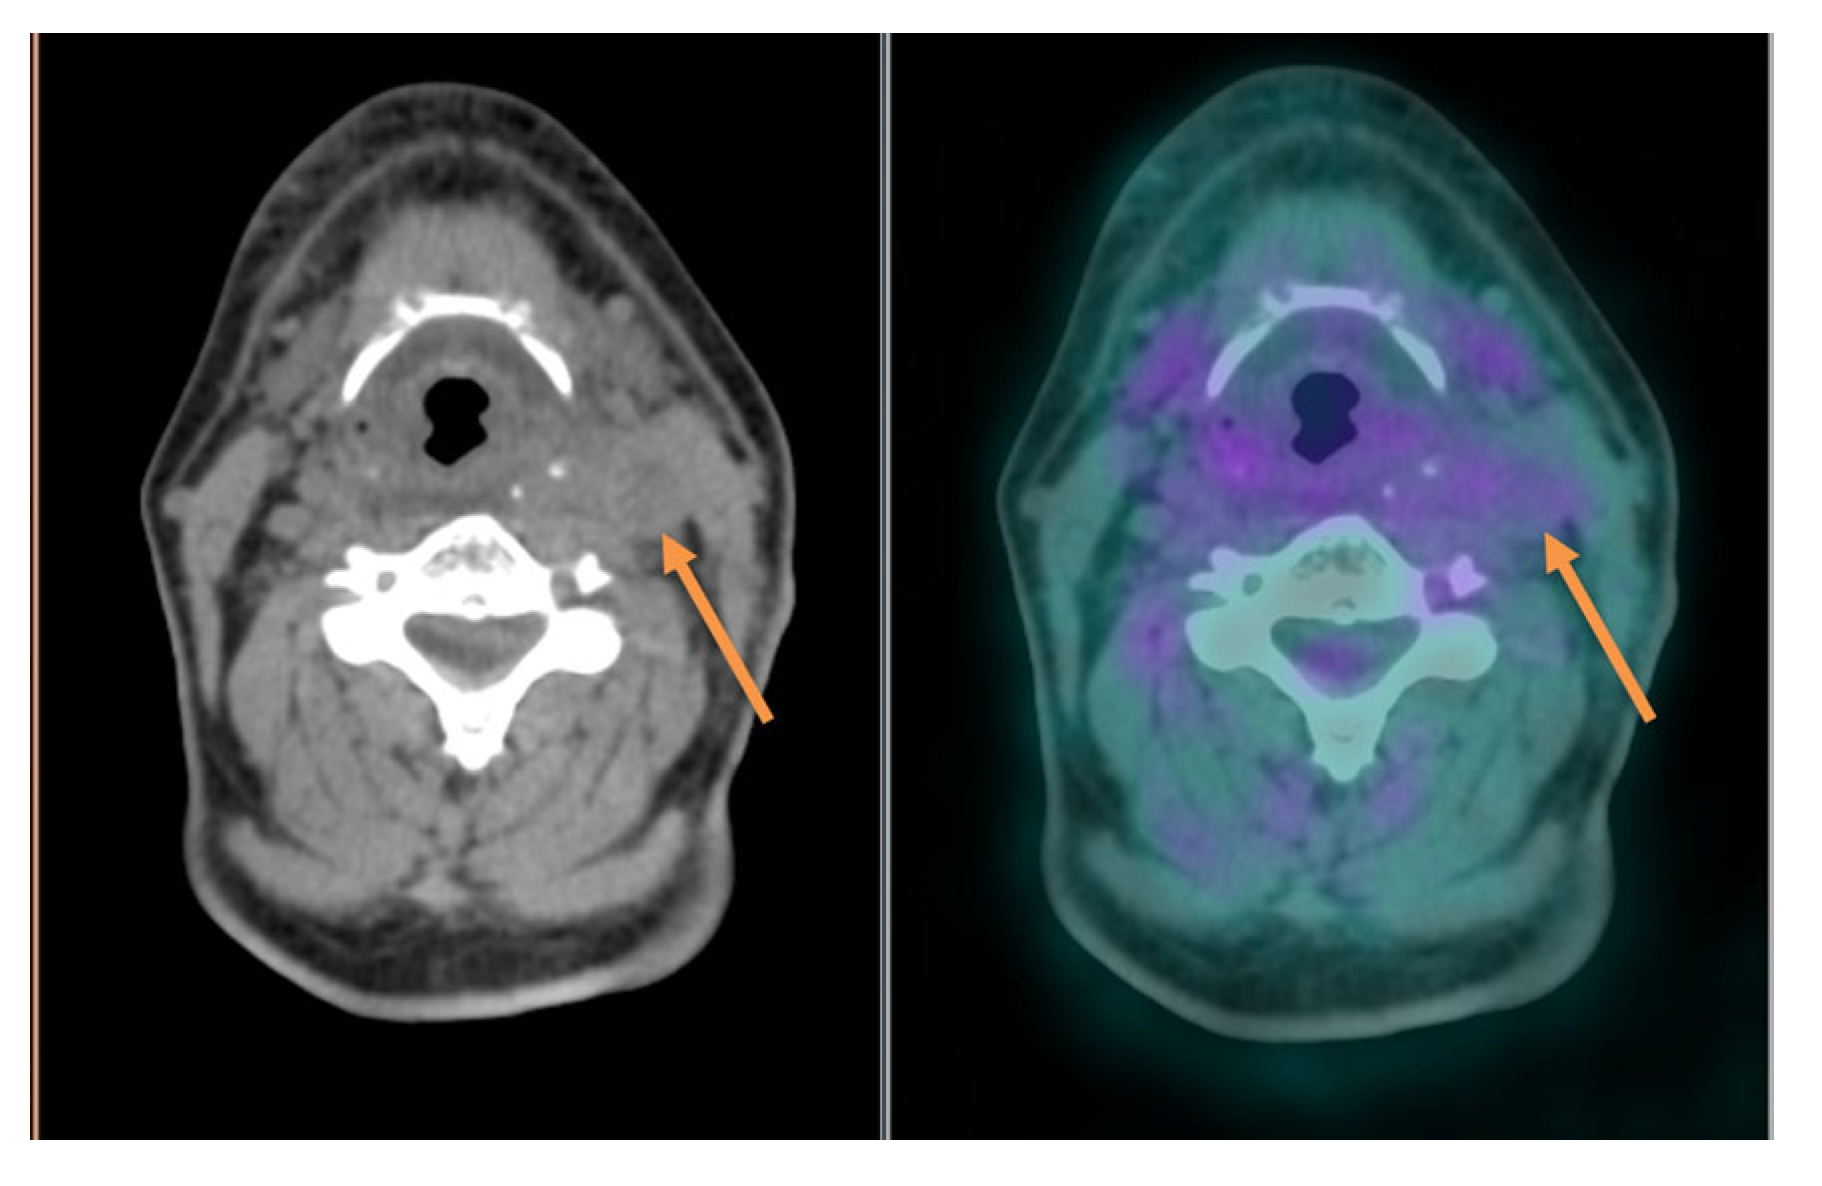

- Helsen, N.; Van den Wyngaert, T.; Carp, L.; De Bree, R.; VanderVeken, O.M.; De Geeter, F.; Maes, A.; Cambier, J.P.; Spaepen, K.; Martens, M.; et al. Quantification of 18F-fluorodeoxyglucose uptake to detect residual nodal disease in locally advanced head and neck squamous cell carcinoma after chemoradiotherapy: Results from the ECLYPS study. Eur. J. Nucl. Med. Mol. Imaging 2020, 47, 1075–1082. [Google Scholar] [CrossRef]